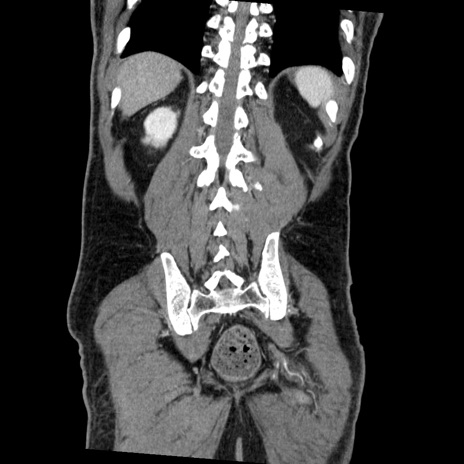

症例22(冠状断像)

【症例】50歳代男性

【主訴】腹痛

【現病歴】AVMからの被殻出血のため回復期リハ病棟入院中。 本日午後3時頃急に下腹部痛が出現した。

【既往歴】AVM、被殻出血、虫垂炎、高血圧

【身体所見】意識晴明、左半身不全麻痺、会話の理解は良好、36.5°C、腹部:膨隆、全体に板状硬、下腹部正中に圧痛点あり、反跳痛-、筋性防御不明、右下腹部にope scar

【データ】WBC 9400、CRP 0.06